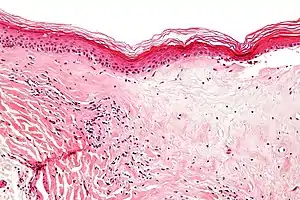

| Micrograph of lichen sclerosus showing the characteristic subepithelial sclerosus (right/bottom of image). H&E stain. | |

A biopsy of the affected skin can be done to confirm diagnosis. When a biopsy is done, hyperkeratosis, atrophic epidermis, sclerosis of dermis and lymphocyte activity in dermis are histological findings associated with LS.[22] The biopsies are also checked for signs of dysplasia.[23]